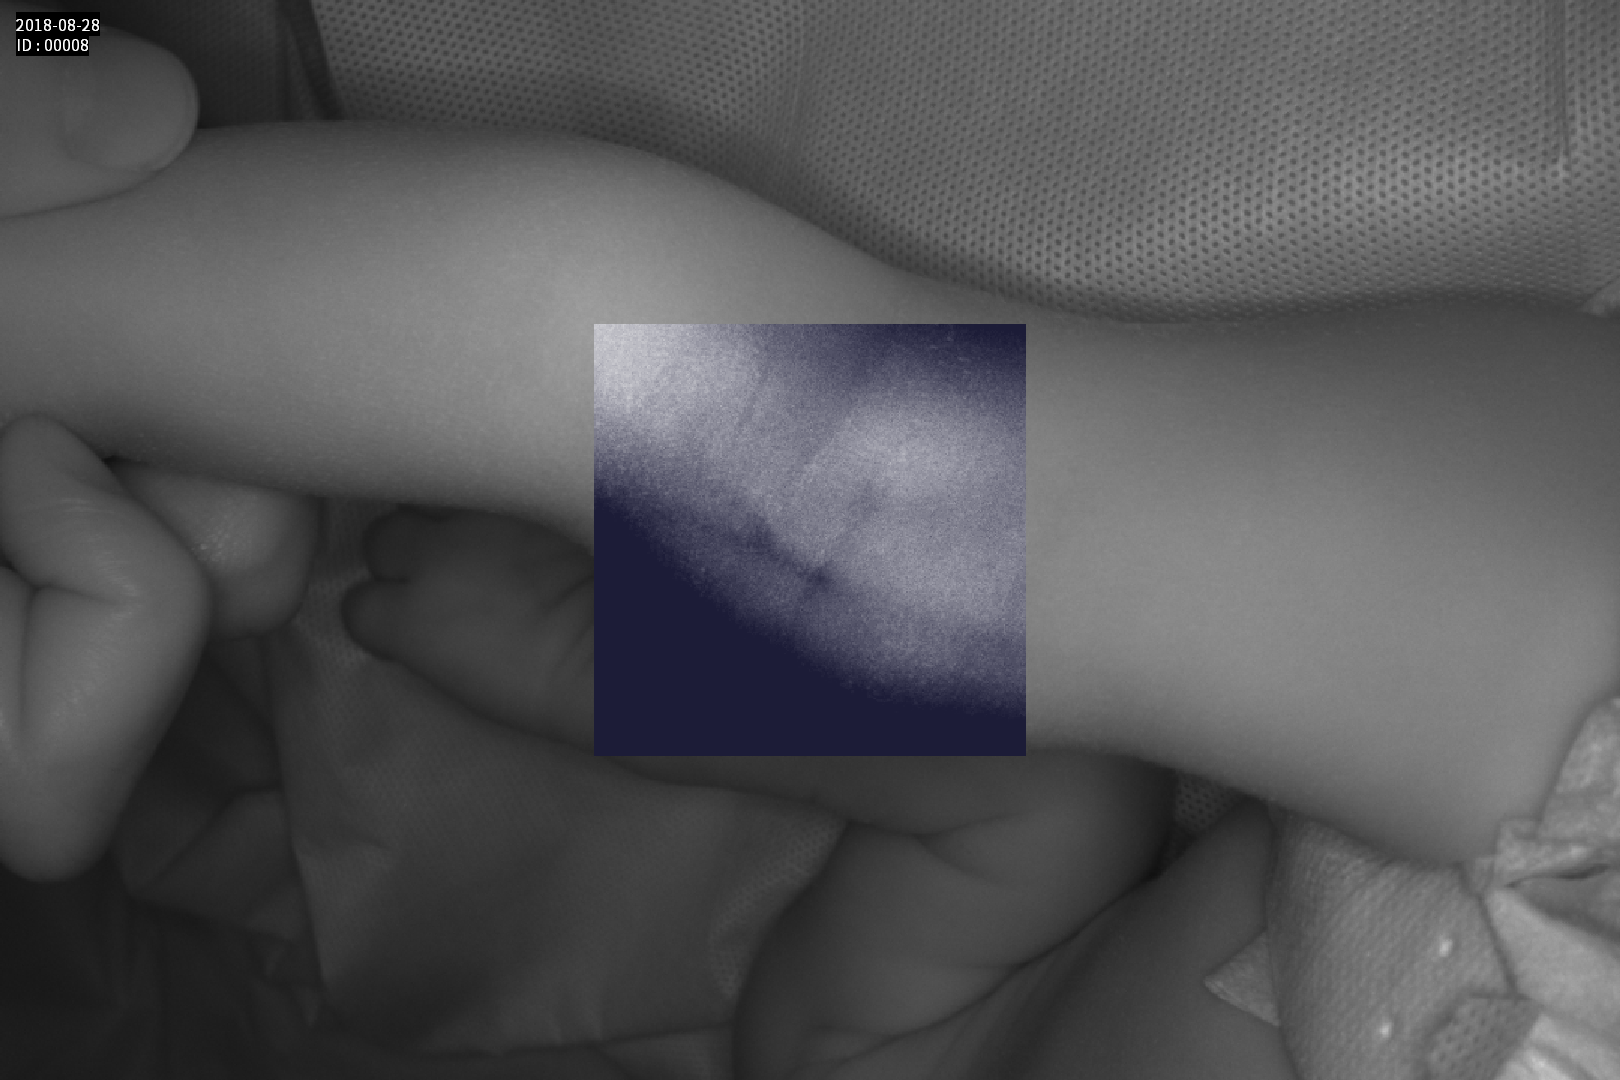

Dispozitiv medical portabil, non-contact, ce ajută la vizualizarea venelor pentru efectuarea puncției venoase, intervențiilor chirurgicale plastice, diagnosticul venelor varicoase.

Grad mare de detecție a venelor greu vizibile până la 10 mm adâncime (inclusiv vene faciale)

Multiple aplicații de vizualizare vene atât la sugari cât și la pacienții obezi sau în urgențe indiferent de tonul de culoare a pielii